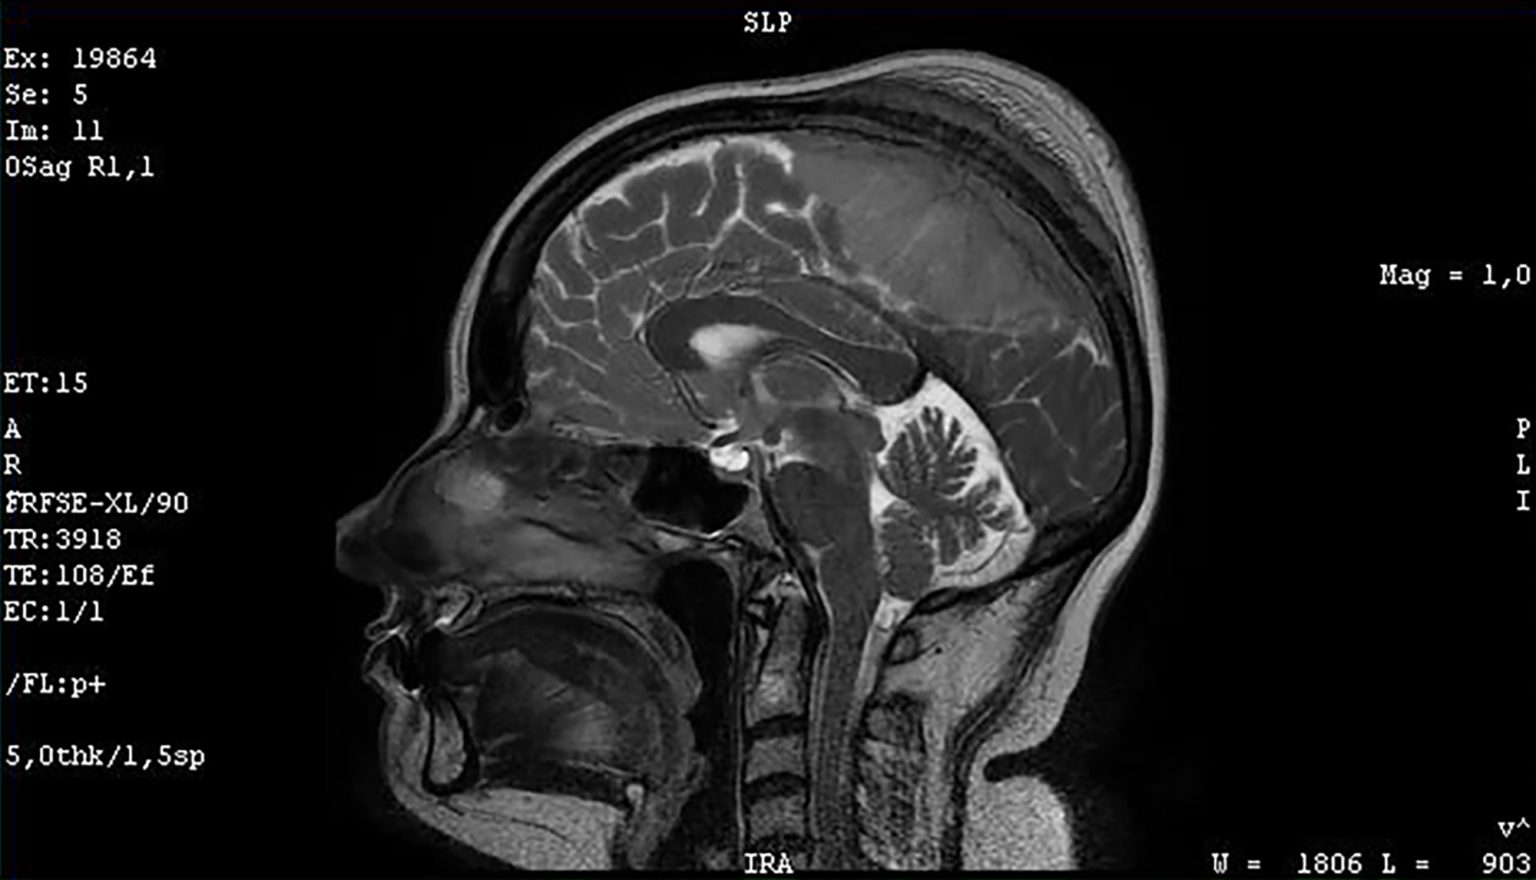

Brain herniation MRI.

Brain herniation.